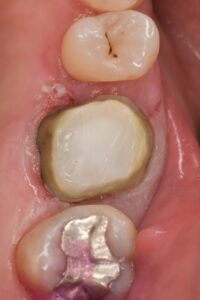

➡むし歯の除去(隔壁作製)、神経の除去と根管内クリーニング、いけたら根管充填とレジンコア(土台)

➡過去の充填物やむし歯の除去と隔壁作製、根管内の充填物の除去とクリーニング